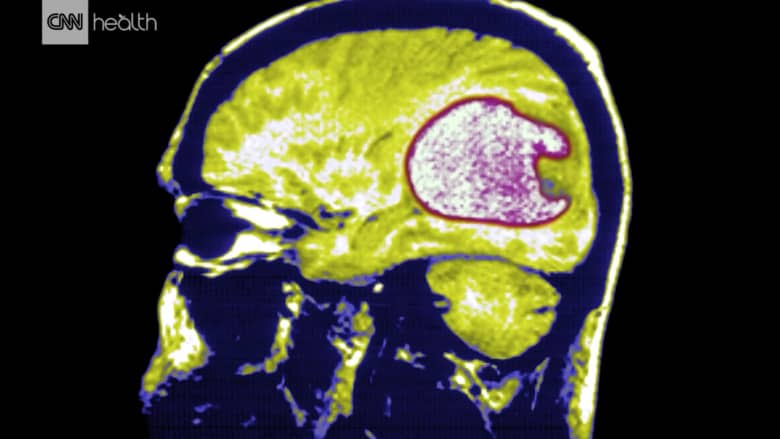

ما هو السرطان الأكثر خبثا الذي يستهدف الدماغ؟

أشارت دراسة عام 2009 من قبل الهيئة الأمريكية للأورام الدماغية إلى أن 10 في المائة من المصابين فقط يتمكنون من العيش لخمس سنوات أو أطول.

أشارت دراسة عام 2009 من قبل الهيئة الأمريكية للأورام الدماغية إلى أن 10 في المائة من المصابين فقط يتمكنون من العيش لخمس سنوات أو أطول.